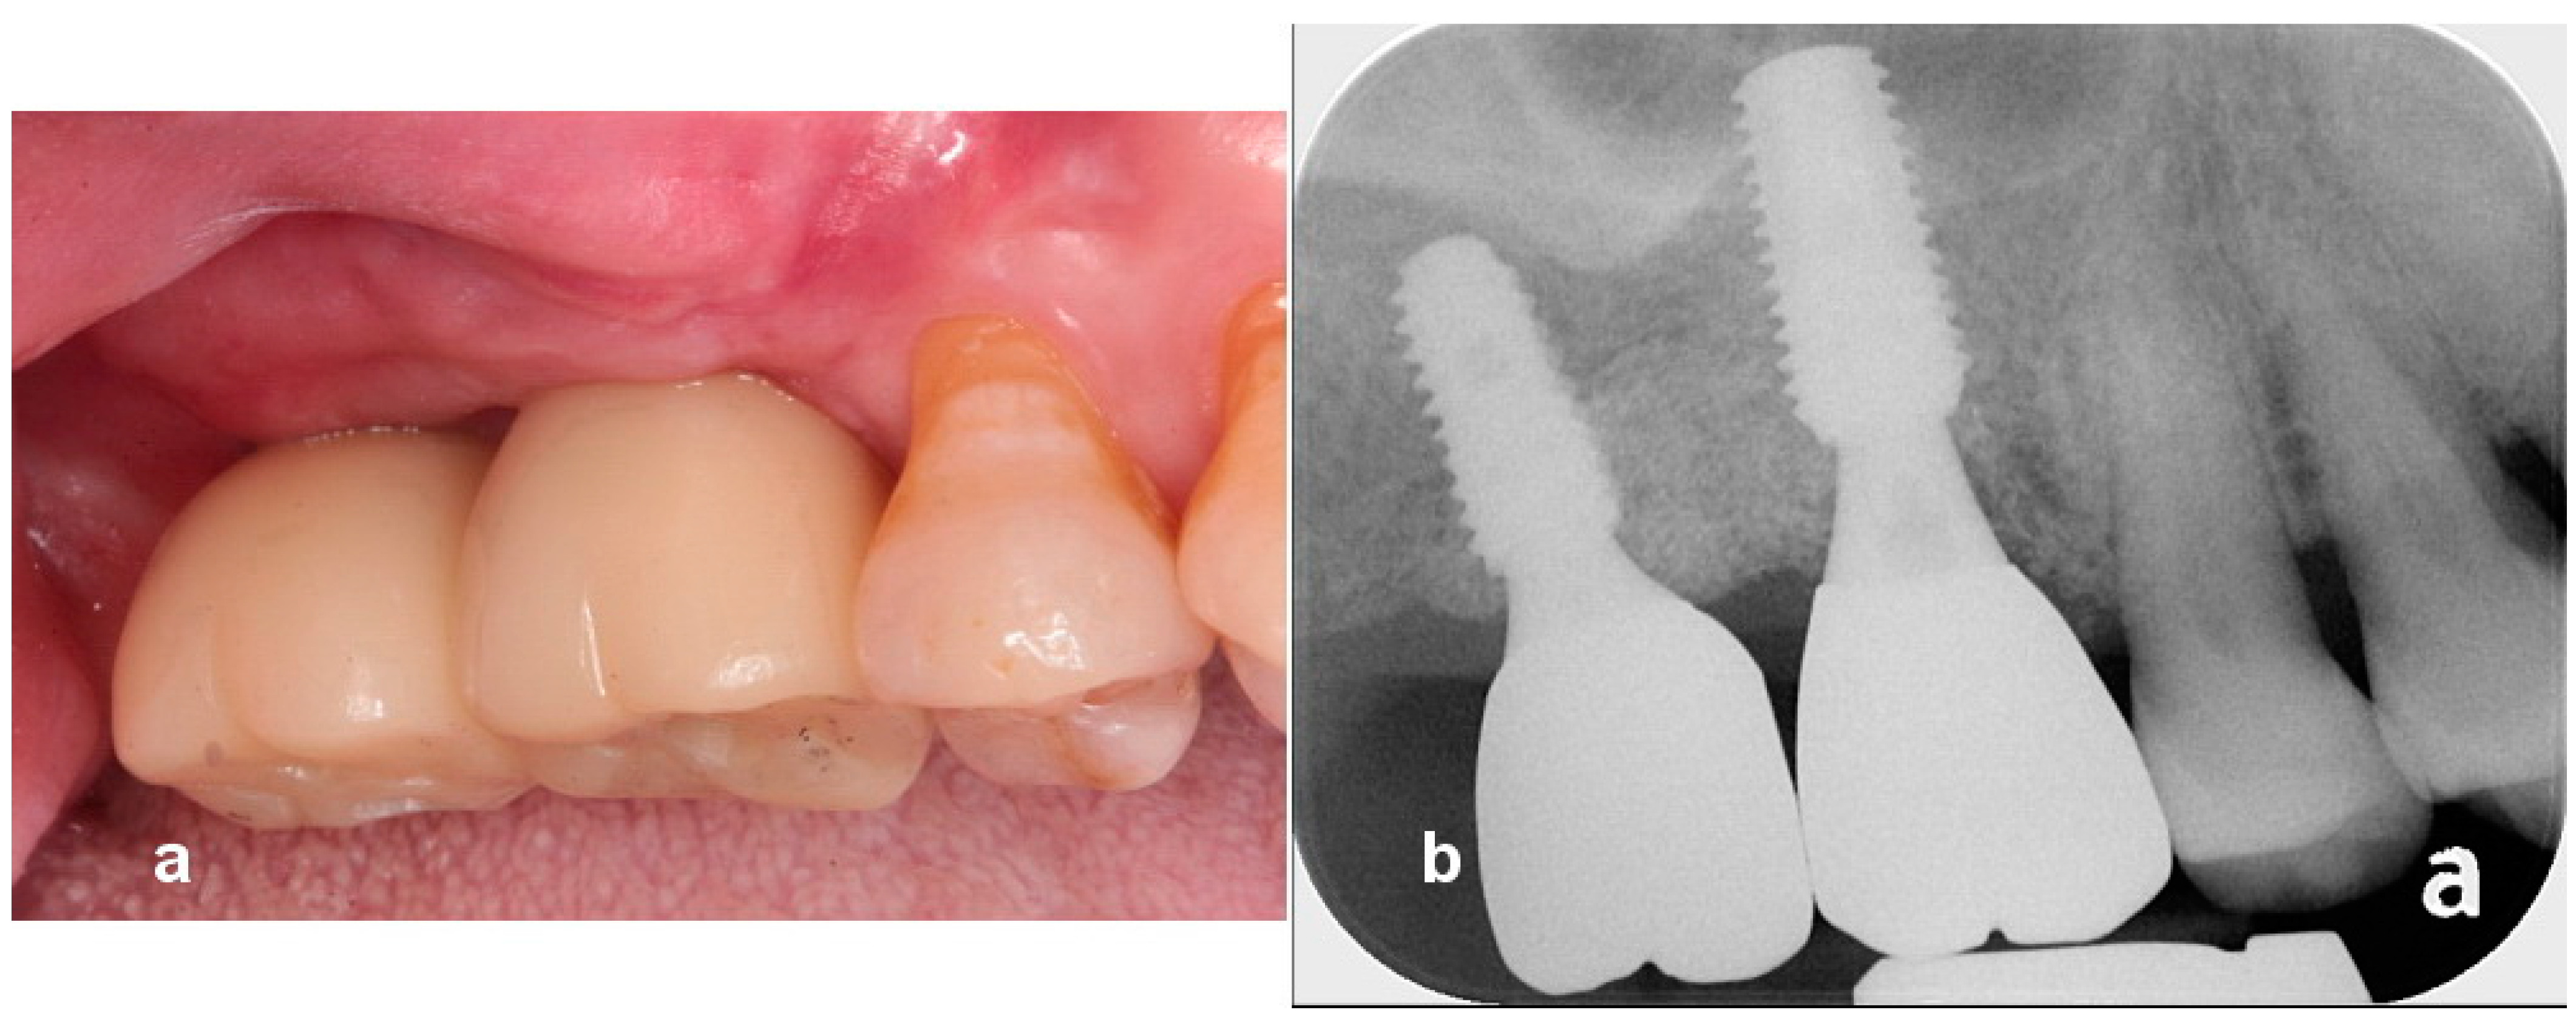

Utilization of Tenting Pole Abutments for the Reconstruction of Severely Resorbed Alveolar Bone: Technical Considerations and Case Series Reports

2. Case Presentations